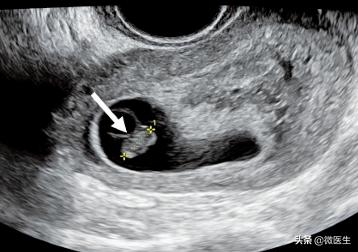

孕8周,经腔内超声检查,胎芽长2.6cm

(6)胚胎停育经腔内超声检査胚胎长度≤5mm,7~10天后复查仍无心管搏动:或胚胎长度>5mm,无心管搏动;或妊娠囊平均内径>20mm,内未见卵黄囊、胎芽,可诊断胚胎停育。

经腹部超声检査胚胎长度≤9m无心管搏动,7~10天后复查仍无心管搏动;或胚胎长度>9m,未能观察胎心搏动;或妊娠囊平均内径>25mm,未见卵黄囊、胎芽,可诊断胚胎停育。

孕9周,经腔内超声检查,胎芽长0.97cm,未见胎心搏动,胚胎停止发育